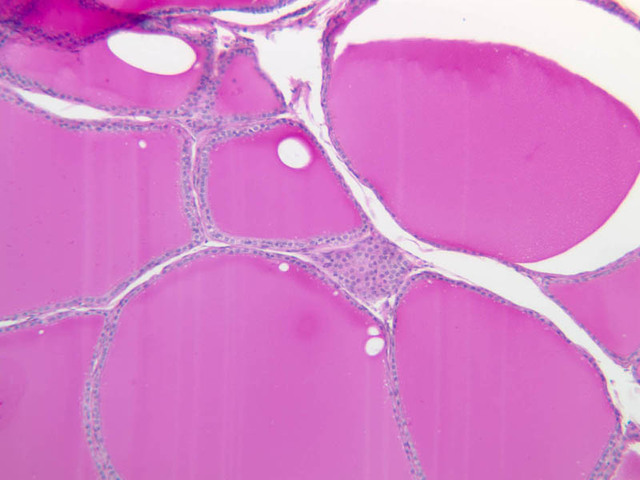

The thyroid gland (slide B-51, lead hematoxylin [10x, 20x, 40x, 40x]; B-52, H&E [10x-labeled, 20x, 40x-labeled, 40x]; B-53, PAS [2.5x, 10x, 20x, 40x]) consists of many closely packed, roughly spherical structures known as follicles, which are enclosed in a thick connective tissue capsule. Connective tissue septa extend from the capsule into the substance of the gland, carrying numerous blood vessels. Follicular cells are arranged as shells of simple cuboidal epithelium surrounding a gelatinous mass known as colloid. Look for a ring of epithelial cells around the homogeneous, pink-staining colloid. The cytoplasm of the follicular cells (principal cells) is faintly basophilic. The follicular cells secrete thyroglobulin, a glycoprotein, which is stored extracellularly in the colloid. In response to TSH, the follicular cells endocytose the colloid and hydrolyze it to form thyroxine. You can see where colloid has been resorbed because this process leaves small holes in the colloid adjacent to the follicular cells. These holes are known as resorption lacunae (B-52 [10x, 20x, 40xlabeled]). Very active follicles may exhibit a columnar epithelium and increased numbers of resorption lacunae. Between follicles, the stroma of the thyroid gland consists of a thin layer of connective tissue and a rich capillary network. Parafollicular cells (light cells or C cells) are located in the connective tissue between follicles or adjacent to follicular cells within follicles. When they lie within the follicular wall, the parafollicular cells do not reach the lumen. Parafollicular cells are slightly larger than the follicular cells and, in H & E preparations, have a more lightly stained cytoplasm (B-52, H&E [10x, 20x, 40x-labeled] [10x-labeled, 20x, 40x-labeled] [10x, 20x, 40x] [10x, 20x, 40x]; B-53, PAS [10x, 20x, 40x]). Parafollicular cells are readily identifiable in slide B-51 (stained with lead hematoxylin), where they appear as purplish-black structures in which the nuclei are difficult to discern (B-51 [10x, 20x, 40x-labeled]). These cells secrete calcitonin, which lowers serum calcium levels by inhibiting bone resorption and accelerating osteoid calcification.

B51, Thyroid, 10x (Pb) B51, Thyroid, 20x (Pb) B51, Thyroid, 40x (Pb) B51, Thyroid, 40x (Pb) B52, Thyroid, 10x Labeled (H&E) B52, Thyroid, 20x (H&E) B52, Thyroid, 40x Labeled (H&E) B52, Thyroid, 40x (H&E) B53, Thyroid, 2.5x (PAS) B53, Thyroid, 10x (PAS) B53, Thyroid, 20x (PAS) B53, Thyroid, 40x (PAS) B52, Thyroid, 10x (H&E) B52, Thyroid, 20x (H&E) B52, Thyroid, 40x Labeled (H&E) B52, Thyroid, 10x (H&E) B52, Thyroid, 20x (H&E) B52, Thyroid, 40x Labeled (H&E) B52, Thyroid, 10x Labeled (H&E) B52, Thyroid, 20x (H&E) B52, Thyroid, 40x Labeled (H&E) B52, Thyroid, 10x (H&E) B52, Thyroid, 20x (H&E) B52, Thyroid, 40x (H&E) B52, Thyroid, 10x (H&E) B52, Thyroid, 20x (H&E) B52, Thyroid, 40x (H&E) B53, Thyroid, 10x (PAS) B53, Thyroid, 20x (PAS) B53, Thyroid, 40x (PAS) B51, Thyroid, 10x (Pb) B51, Thyroid, 20x (Pb) B51, Thyroid, 40x Labeled (Pb)